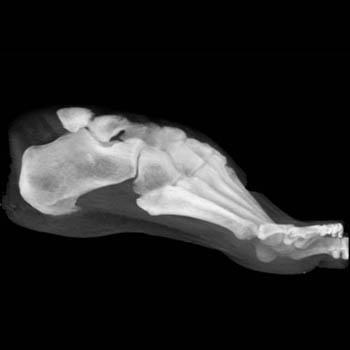

Radiographic findings on CT (Figure: OA of the foot) are the same as those detected by conventional radiographs, including subchondral sclerosis, asymmetric or nonuniform joint space narrowing, osteophytes, subchondral cysts, and in some cases osteocartilaginous intrarticular fragments. In addition, plantar and posterior calcaneal spurs are manifestations of degenerative joint disease; although, they are often asymptomatic.